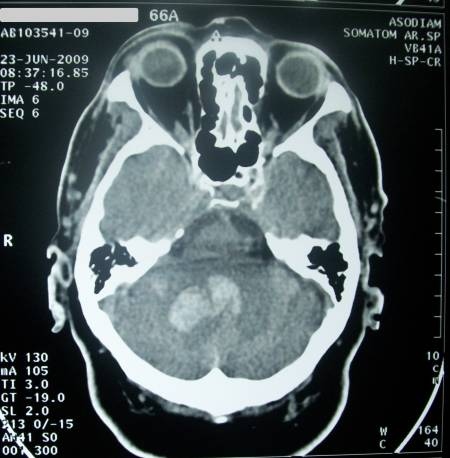

TAC que muestra un caso de accidente cerebrovascular hemorrágico. (Foto: DICYT)

El tiempo medio de demora prehospitalaria fue 714,26 minutos. Factores como tener mayor edad, presentar problemas con el habla, solicitar ayuda de forma inmediata tras el inicio de los síntomas, pensar que lo que estaba padeciendo era un ictus o activar el Servicio de Emergencias se relacionaron con un menor retraso prehospitalario.

Por otros lado, el ser fumador activo, pensar que la situación podía mejorar de manera espontánea sin necesidad de pedir ayuda o presentar mayor retraso de decisión se relacionaron con un incremento en el tiempo que el paciente empleaba en acudir al hospital. El inicio gradual de los síntomas, un nivel de ansiedad leve-moderado, el inicio nocturno de los síntomas o un retraso de decisión superior a 15 minutos fueron los principales factores que predijeron un retraso prehospitalario mayor.